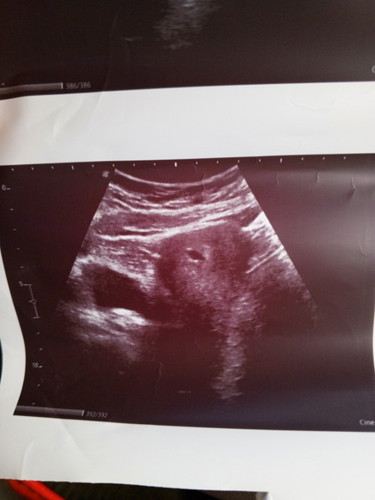

ประจำเดือนมาครั้งสุดท้าย 9/8/67 ซึ่งนับได้7วีค1วัน แต่วันนี้คุณหมอซาวด์ได้5วีค เจอแต่ถุงการตั้งครรภ์

ปกติค่ะ เราอาจจะไม่ได้ตั้งครรภ์ ตั้งแต่ประจำเดือนหมดค่ะ อาจจะตั้งหลังจากนั้นก็ได้